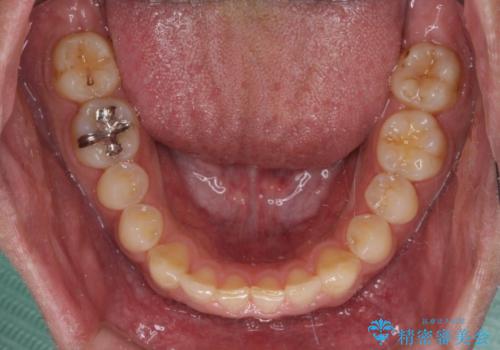

深い咬み合わせと隙間の空いた歯列をワイヤー矯正で改善

- 前歯の隙間と深い咬み合わせを改善したいとのことで来院された患者様です。

マウスピース矯正の自己管理が面倒とのことで、ワイヤー矯正により治療を行うこととしました。

奥歯の咬み合わせは理想的な状態であったため、ワイヤー矯正でもインビザラインでも比較的容易に対応可能でした。